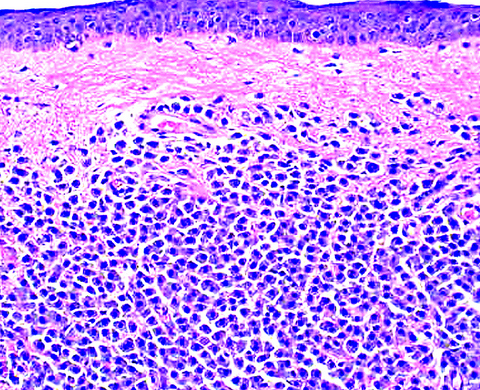

Microscopic (histologic) description

- Within the macules and plaque, mast cells are predominantly in papillary dermis

- Mast cells are round or spindle shaped with abundant eosinophilic cytoplasm, distinct cytoplasmic boundaries, large pale nuclei

- Eosinophils are often present

- Also edema of papillary dermis, subepidermal vesiculation

Microscopic (histologic) images